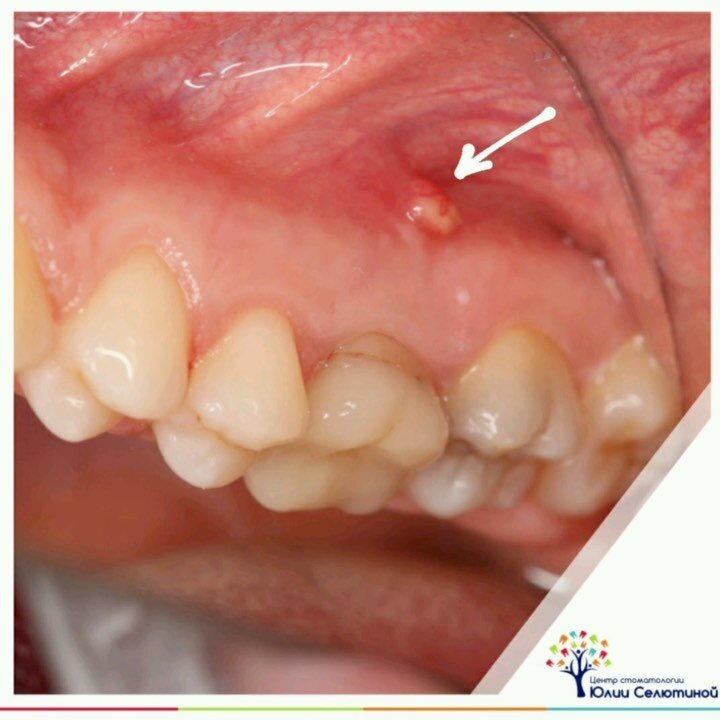

Свищ: что делать?

Свищ от молочного зуба - показание для удаления. А что делать с постоянным?  Лечение свища на постоянном зубе направлено исключительно на сохранение этого самого причинного зуба. Свищ на десне образуется при воспалении в области верхушки корня, т.е. когда оно уже вышло за пределы зуба. Это называется периодонтит. А свищевой ход возникает, когда организм пытается вывести гнойное отделяемое наружу. Этот воспалительный процесс не возникает мгновенно, он может хронически расти годами. Прорыв случается, когда иммунитет человека снижен, например, во время инфекционного заболевания. Организм больше не может сдерживать воспаление, и оно ищет выход наружу. Самое простое — это проложить путь через десну. • Свищ — это симптом воспаления внутри костной ткани под или над зубом, это гнойный процесс. Самое печальное в нем (для врачей) то, что он никак не беспокоит и не болит даже при надавливании. Свищ может периодически прорывать, а гной вытекать в полость рта. От этого ничего хорошего не будет. Р

• Свищ — это симптом воспаления внутри костной ткани под или над зубом, это гнойный процесс.

Самое печальное в нем (для врачей) то, что он никак не беспокоит и не болит даже при надавливании.

Свищ может периодически прорывать, а гной вытекать в полость рта.